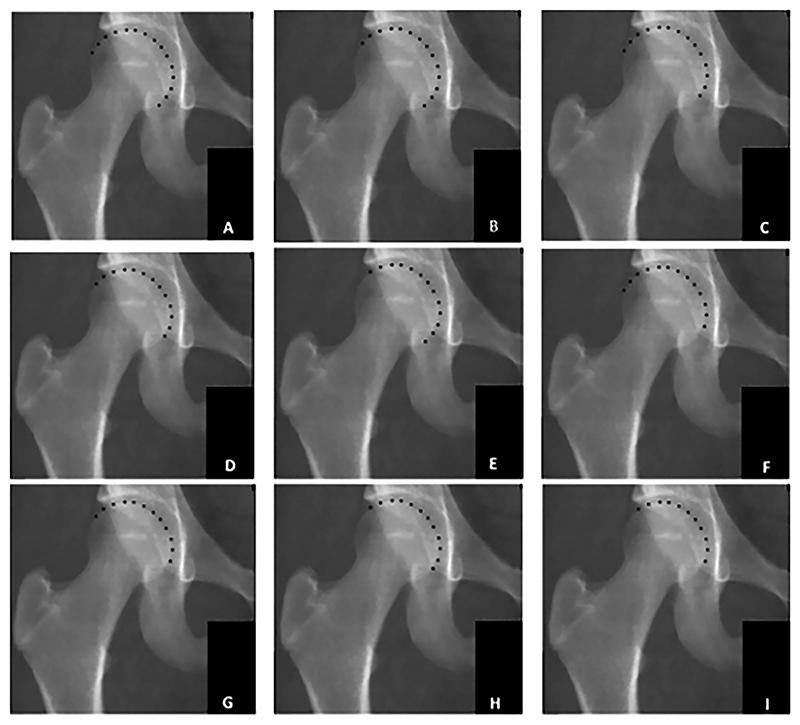

The aim of this study is to present a newly developed automated method to determine radiographic measurements of hip morphology on dual-energy x-ray absorptiometry (DXA) images. The secondary aim was to compare the performance of the automated and manual measurements.

30 DXA scans from 13-year-olds of the prospective population-based cohort study Generation R were randomly selected. The hip shape was outlined automatically using radiographic landmarks from which the acetabular depth-width ratio (ADR), acetabular index (AI), alpha angle (AA), Wiberg and lateral center edge angle (WCEA) (LCEA), extrusion index (EI), neck-shaft angle (NSA), and the triangular index (TI) were determined. Manual assessments were performed twice by two orthopedic surgeons. The agreement within and between observers and methods was visualized using Bland-Altman plots, and the reliability was studied using the intraclass correlation coefficient (ICC) with 95 % confidence intervals (CI).